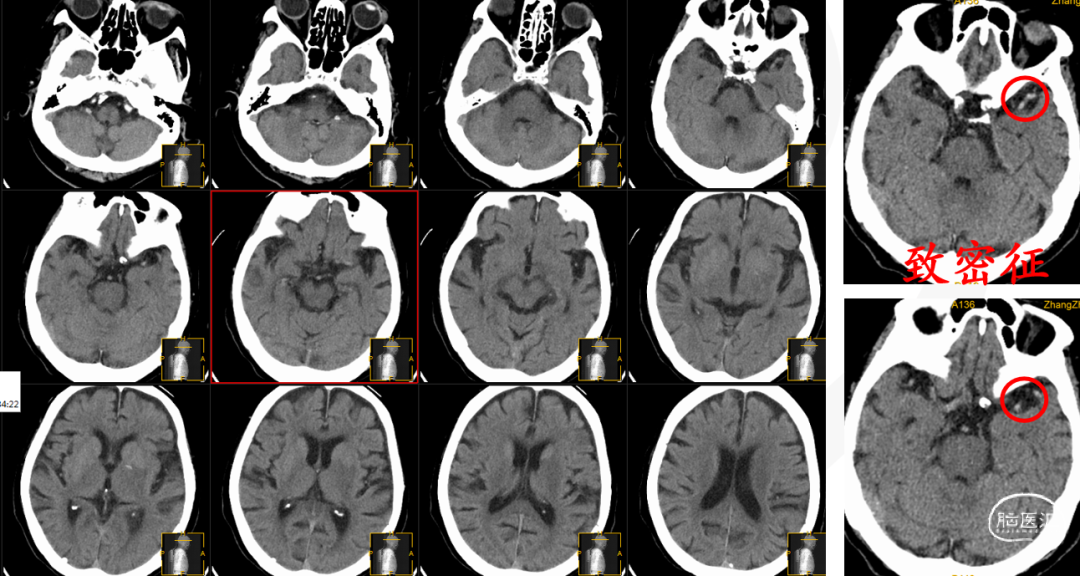

影像信息

动脉早期冠状位残端

动脉早期水平位残端

颅脑CT平扫

CTA

多模式影像学评估可协助血管闭塞性质的判断,特别是多时相CTA扫描;